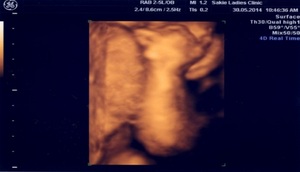

院内に導入された「4D(フォーディ)エコー」は、超音波で、白黒の一断面を合成し色をつけて立体的にして、子宮内の様子を写しだす検査。妊娠週が進めば、指を吸ったり、あくびをしたりする赤ちゃんの顔や動作までがわかります。「お腹の中の赤ちゃんの動きをリアルに視て、母親であることを実感するという効果の他に、妊娠期の母体の状態をも写しだします。羊水をナミナミとたたえている子宮の赤ちゃんは、4Dエコーで鮮明に映し出されますが、ストレスなどで羊水が少ないと、赤ちゃんは骨盤の中に埋もれてしまいます。姿勢が悪くて骨盤がねじれたり、食生活も大きく影響を与えたりしますので、妊娠期の生活のフォローは本当に大事です」

4Dエコー画像 羊水が ナミナミの子宮内の赤ちゃん

左:16週 頭と顔が見えます 右:15週 頭を触っています

羊水ナミナミでない子宮内の赤ちゃん 26週 腕がみえます

28週 羊水ナミナミの赤ちゃん 顔と腕 背中がみえます